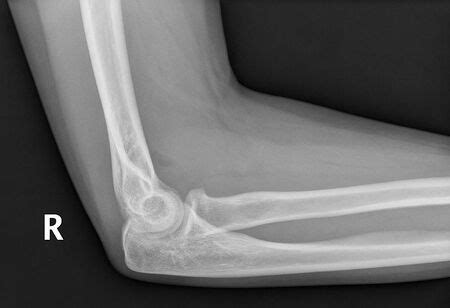

Elbow Sail Sign. Will be higher in the throwing athlete. Web the posterior fat pad sign is the visualization of a lucent crescent of fat located in the olecranon fossa on a true lateral view of an elbow joint with the elbow flexed at a right angle indicating an elbow joint effusion.

Will be higher in the throwing athlete. In full extension, normal carrying angle is ~11 degrees in men and ~13 degrees in women. Web there is elevated anterior fat pad of the elbow due to joint effusion which is called sail sign. Web an abnormal anterior fat pad is described as a sail sign because it is unusually prominent and bows outward to form a triangular shape. Web position of maximal elbow capsular distension. It indicates the presence of an elbow joint effusion. After trauma, blood can accumulate in the intraarticular space and push the fat pad anteriorly; Includes a description of the sail sign and posterior fat pad sign. Anterior and posterior fat pad signs (in a case of an undisplaced fracture of the radius head which is not visible directly). Web the posterior fat pad sign is the visualization of a lucent crescent of fat located in the olecranon fossa on a true lateral view of an elbow joint with the elbow flexed at a right angle indicating an elbow joint effusion.

Includes a description of the sail sign and posterior fat pad sign. Web there is elevated anterior fat pad of the elbow due to joint effusion which is called sail sign. Will be higher in the throwing athlete. Normally, the posterior fat pad will not be seen in this view ref. Web an abnormal anterior fat pad is described as a sail sign because it is unusually prominent and bows outward to form a triangular shape. In adults, this is usually a radial head fracture whereas in children, the commonest cause of a raised elbow fat pad is a supracondylar fracture. Web position of maximal elbow capsular distension. Web the fat pad sign, also known as the sail sign, is a potential finding on elbow radiography which suggests a fracture of one or more bones at the elbow. Web the posterior fat pad sign is the visualization of a lucent crescent of fat located in the olecranon fossa on a true lateral view of an elbow joint with the elbow flexed at a right angle indicating an elbow joint effusion. When this occurs, the olecranon acts as a fulcrum after engaging in the olecranon fossa. It is may indicate an occult fracture that is not directly visible.